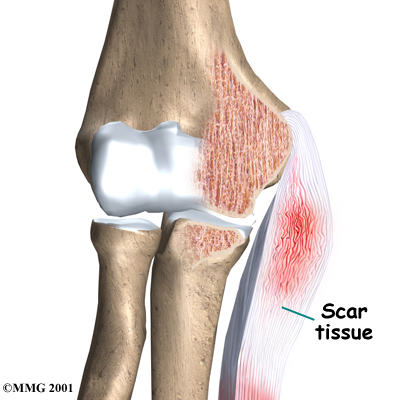

Instead of inflammatory cells, the body produces a type of cells called fibroblasts. When this happens, the collagen loses its strength. It becomes fragile and can break or be easily injured. Each time the collagen breaks down, the body responds by forming scar tissue in the tendon. Eventually, the tendon becomes thickened from extra scar tissue.

No one really knows exactly what causes tendonosis. Some doctors think that the forearm tendon develops small tears with too much activity. The tears try to heal, but constant strain and overuse keep re-injuring the tendon. After a while, the tendons stop trying to heal. The scar tissue never has a chance to fully heal, leaving the injured areas weakened and painful.

Scar Tissue